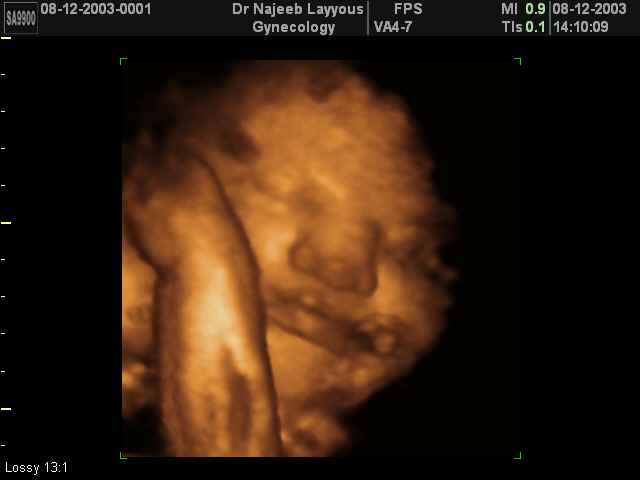

صور لوجه الجنين بجهاز الالتراساوند ثلاثي الأبعاد | الدكتور نجيب ليوس

صور لوجه الجنين بجهاز الموجات فوق صوتية ثلاثي الأبعاد